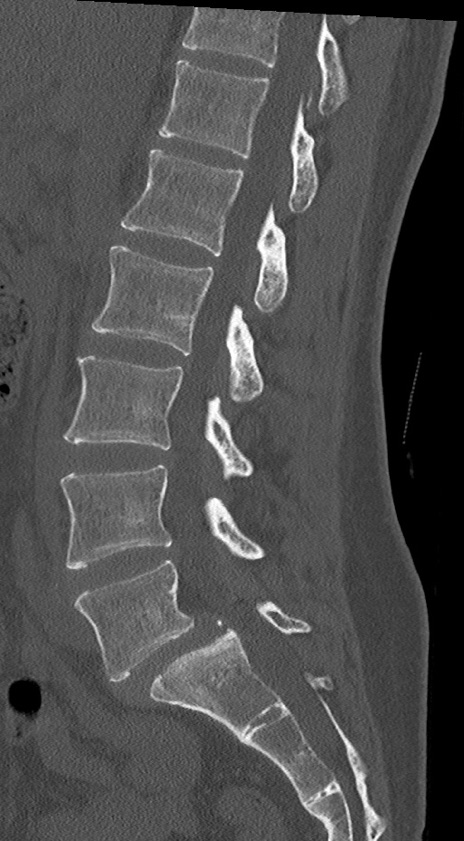

【整形】TIPS症例4 腰椎CT(矢状断像)

腰椎CT

冠状断像